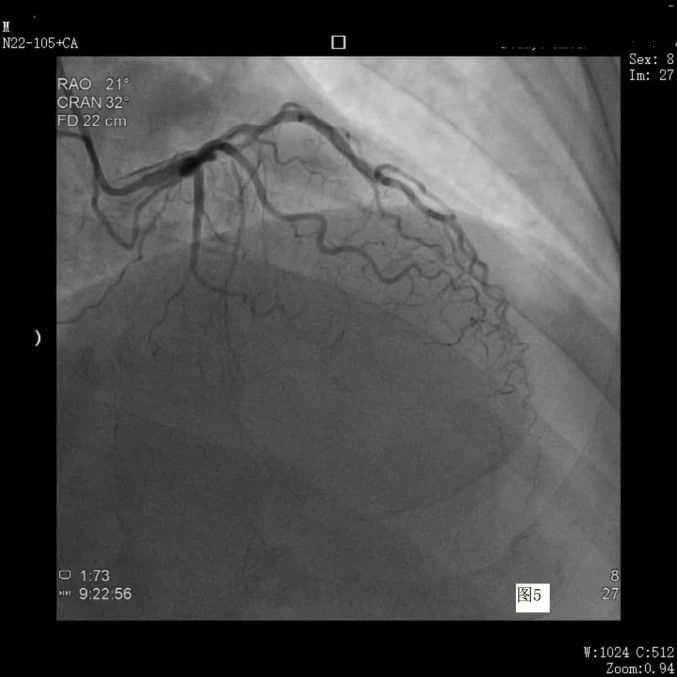

7月27日,患者“经桡动脉心脑血管同时造影术”在导管室进行。术中,神经外科一病房团队首先进行脑血管造影,心内科团队随后完成心血管造影。

冠脉造影见右冠支架术后良好

左侧冠脉与上次狭窄程度无变化